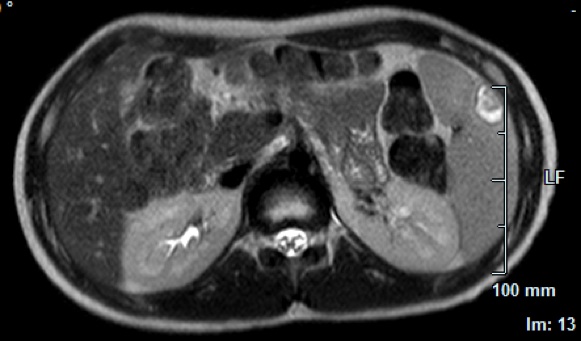

Eseguiamo quindi un'ecografia addominale (Figura 3): �Milza

ingrandita e disomogenea con alcune areole rotondeggianti,

sfumatamente ipoecogene. All'ilo epatico presenza di alcuni linfonodi

ingranditi ovalariformi.�